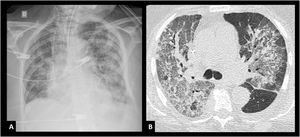

Conceptually, ARDS consists in an acute respiratory failure caused by inflammatory pulmonary edema, characterized by increased vascular permeability with extravasation of fluids into the interstitial space with consequent flooding of the alveolar spaces.1 The loss of aerated lung tissue, due to atelectasis in gravity-dependent areas produced by the increased weight of the overlying lung tissue, leads to profound oxygenation impairment secondary to increased intrapulmonary shunt and alveolar dead space, along with a marked decrease in respiratory system compliance. ARDS is also characterized by the presence of lung infiltrates on CXR (CXR) and computed tomography (CT) scans (Fig. 1A and B). Anatomically and pathologically, the main feature of ARDS is an histological pattern known as diffuse alveolar damage (DAD), which includes the presence of hyaline membranes, edema, type I and II alveolar cell necrosis, and hemorrhage.2,3 This description constitutes the "conceptual model of ARDS" and reflects how clinicians "perceive" the syndrome.4

Chest imagesImaging criteria should include bilateral infiltrates on CXR or CT. Additionally, lung ultrasound (evidence of B-lines or consolidation, Fig. 2A and B) is incorporated in this update. Whichever modality is used, it should suggest loss of aeration not fully explained by lobar collapse, pulmonary nodules or pleural effusion.